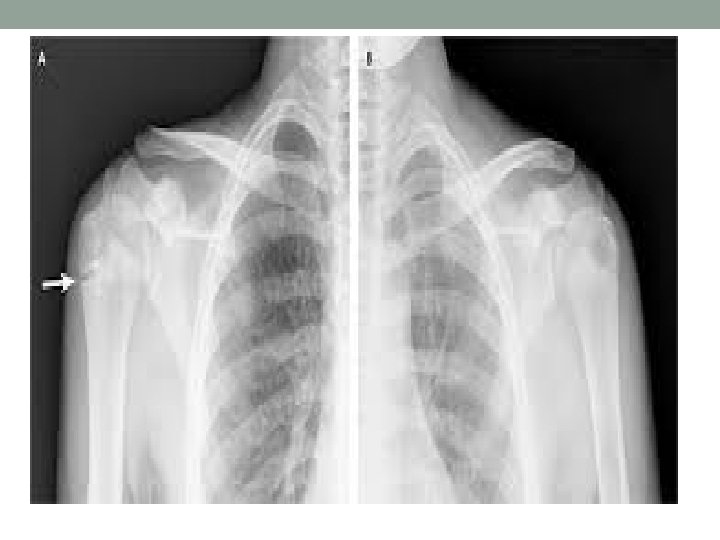

Little Leaguer’s Shoulder • Olsen et al. • 6 innings with 7. 9 months versus 4 innings with 5. 5 months • 11 -13 years of age • Proximal humeral physis • Repetitive rotational stress

Little Leaguer’s Shoulder Management • Radiographs-Gasser & Carson • Widening • Sclerosis • Cystic changes • Treatment • Progressive throwing program • Proper mechanics • 3 months